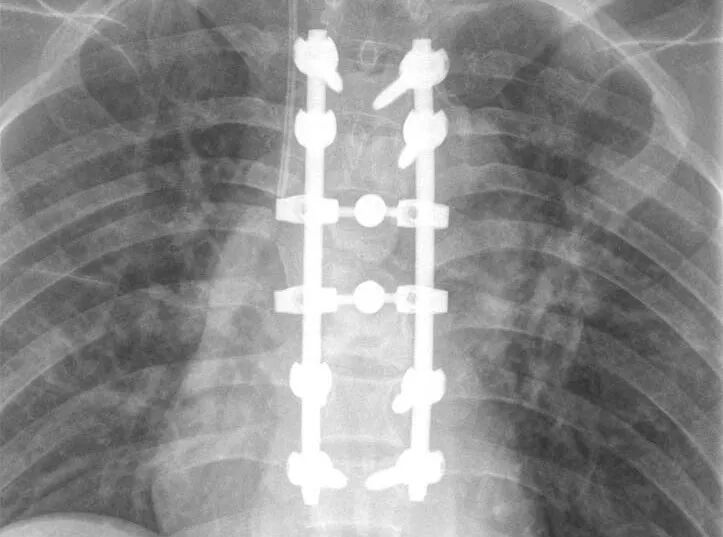

胸椎结核是因为结核菌侵蚀胸椎椎体造成的骨质破坏以及化脓性病变,一般患者会有全身症状。胸椎结核还是一种慢性骨科疾病,会侵蚀骨质和软组织,破坏骨质,并造成软组织的增生。背部痛是胸椎结核最常见的症状,疼痛的性质多为钝痛或酸痛,并且还伴有压痛及叩击痛。胸椎结核的具体症状表现有:疼痛、脊柱活动受限、肿胀、功能障碍、畸形等。

胸椎结核和其他脊柱结核一样易发于椎体,以破坏脊柱的前柱、中柱为主。而且,又因其本身存在的生理性后凸,应力集中在椎体的前侧, 患者负重后容易造成椎体塌陷,从而就导致后凸畸形十分的明显。结核杆菌喜欢生长在血液丰富的地方,人的脊椎椎体以松质骨为主。它的滋养动脉为终末动脉,静脉血流到这里速度缓慢,结核杆菌容易停留在椎体部位。于是,胸椎结核在各方面因素的影响下就产生了。 本期专家推荐